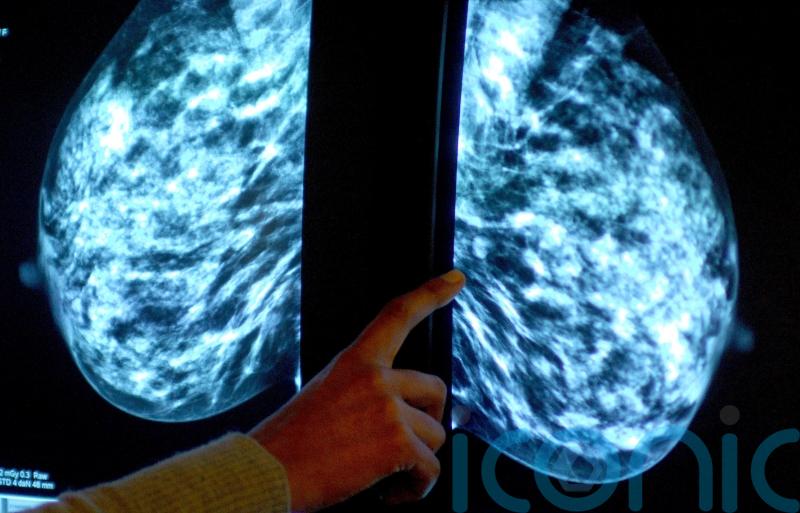

Women who use a contraceptive coil may have a slightly higher risk of developing breast cancer, new research suggests.

The study found an “unexpected” association between the use of an intrauterine system (IUS), also known as an hormonal coil, and an increased risk of the cancer in women aged 15 to 49.

According to the findings, there were 14 extra cases of breast cancer per 10,000 women using a levonorgestrel-releasing intrauterine system (LNG-IUS) for five years, compared with a similar number of women not using the contraception.

Research has found that prolonged use of the contraceptive pill slightly increases breast cancer risk, but it was thought that using the coil would not increase breast cancer risk because of the much lower levels of hormone exposure to the whole body.